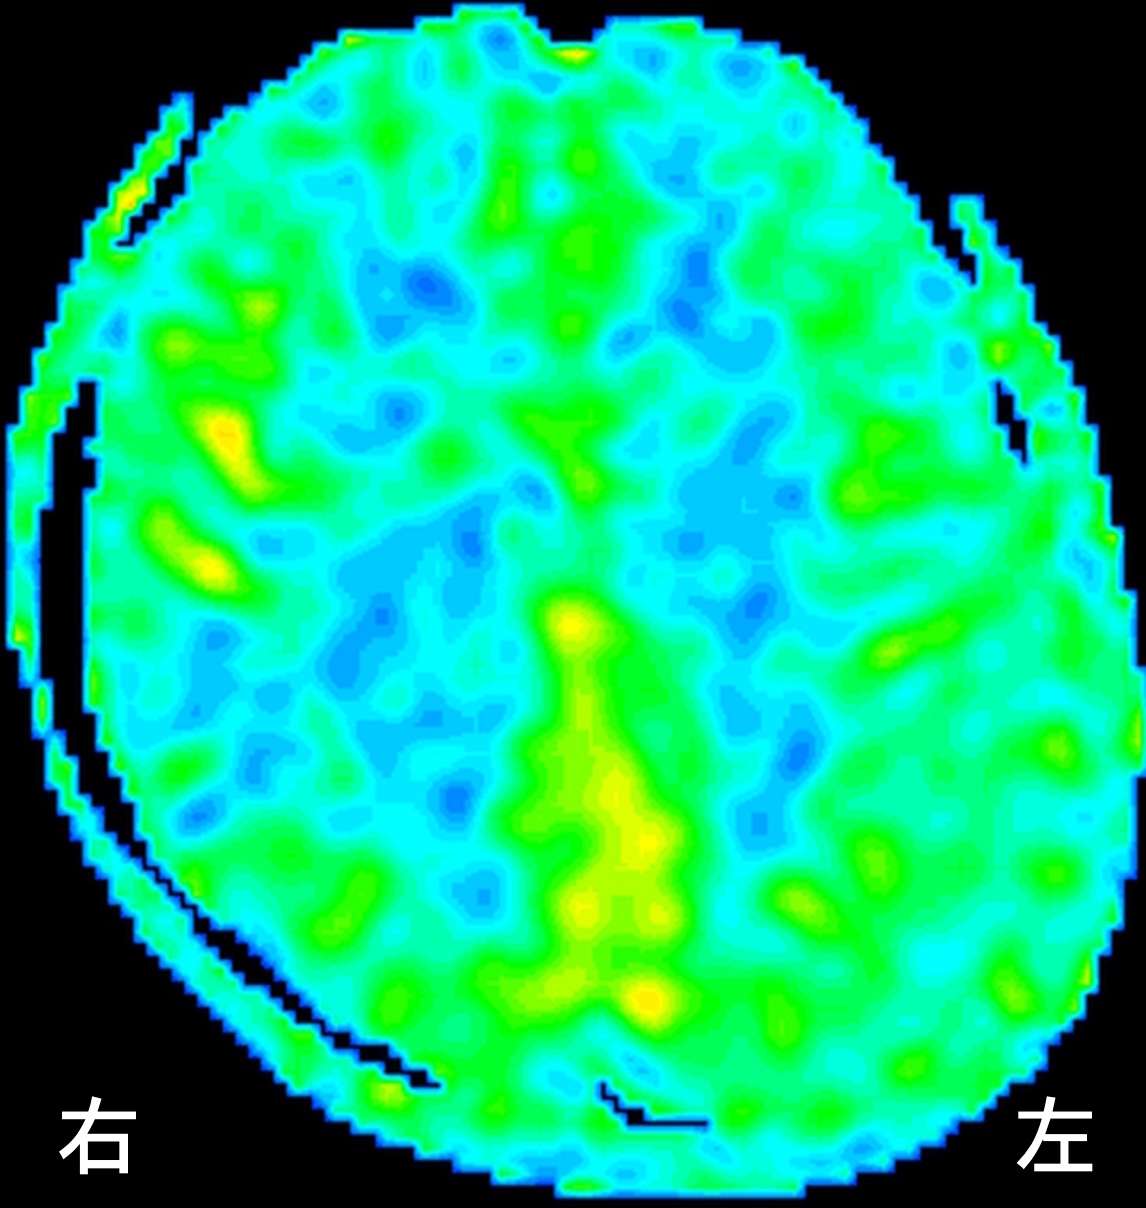

ASL(arterial spin labeling)法という、MRIで脳血流を評価する検査を行ったところ、

右の前頭葉、側頭葉、後頭葉で血流が低下しています。(青い場所が血流の悪い部分です)さらに、時間経過を追って血流の変化を見てみると、

徐々に血流が補われていく状態がうかがえます。